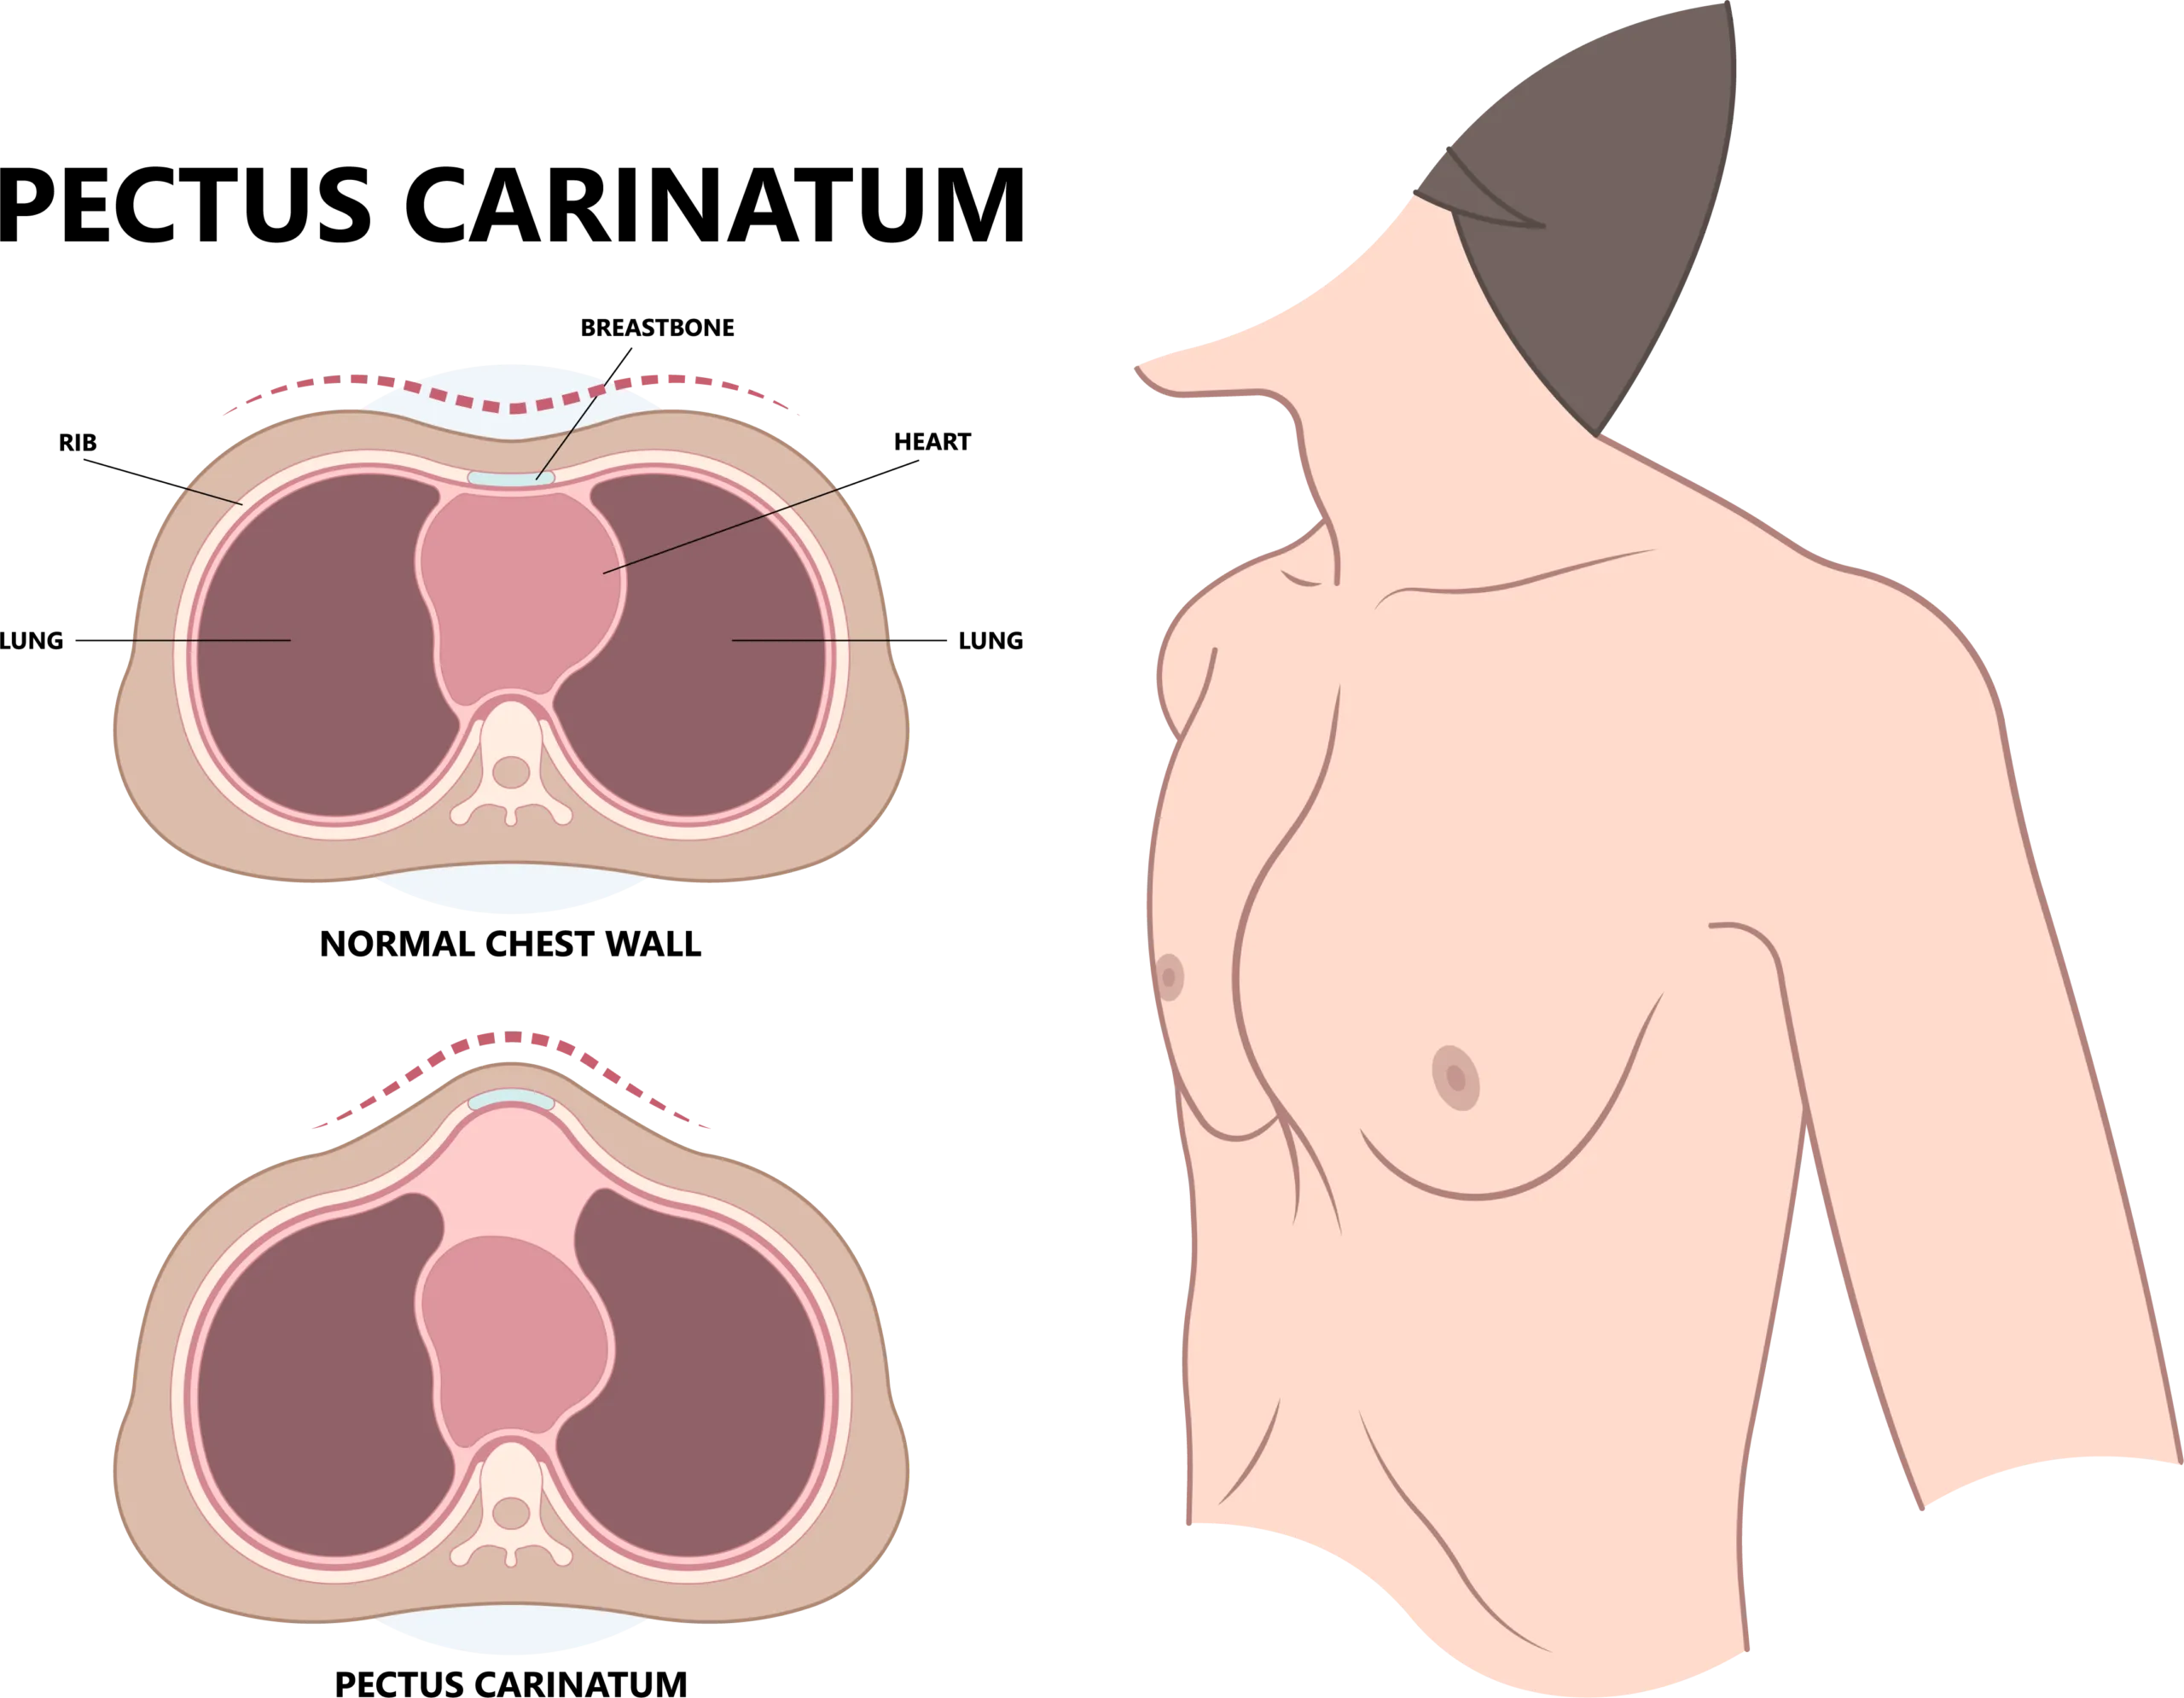

Pectus carinatum is a condition where the breastbone and ribs protrude outward. Our specialized team offers expert evaluation and highly effective, non-surgical bracing treatments to help your child thrive.

Pectus carinatum, sometimes referred to as “pigeon chest,” is a chest wall deformity characterized by an outward protrusion of the sternum (breastbone) and ribs. This occurs due to an overgrowth of the cartilage connecting the ribs to the breastbone. While it is less common than pectus excavatum, it can still cause significant physical and emotional distress for growing children and teenagers.

The gold standard for treating pectus carinatum in children and teens is external compression bracing. Because the chest wall is still flexible during adolescence, a custom-fitted brace can be used to gently apply pressure to the protruding breastbone, gradually reshaping the chest over time. Much like braces straighten teeth.